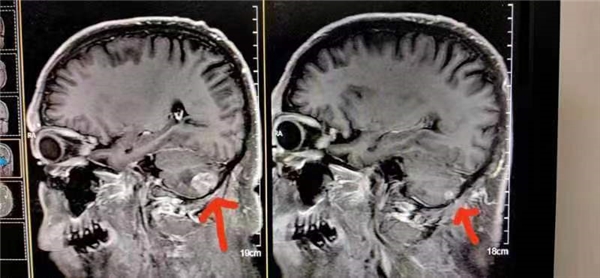

案例24、肺小细胞肺癌脑转移

患者在北京301医院检查治疗结果左脑肿瘤大于右脑肿瘤,陈海林采取采取纯中药的临床治疗,经三个月的治疗,于2023年6月28日的颅脑磁共振平扫十增强:1:右侧小脑转移瘤复查与2o23年3月9日MR片对比,病变基本消失。这个结果连301医院的都声称是奇迹。Case 24: Small cell lung cancer with brain metastasis

The patient underwent examination and treatment at Beijing 301 Hospital, and the results showed that the left brain tumor was larger than the right brain tumor. Chen Hailin adopted clinical treatment with pure Chinese medicine, and after three months of treatment, on June 28, 2023, the brain magnetic resonance plain scan with ten contrasts: 1. Compared with the MR film on March 9, 2023, the right cerebellar metastatic tumor reexamined and the lesion basically disappeared. This result is even claimed to be a miracle by Hospital 301.